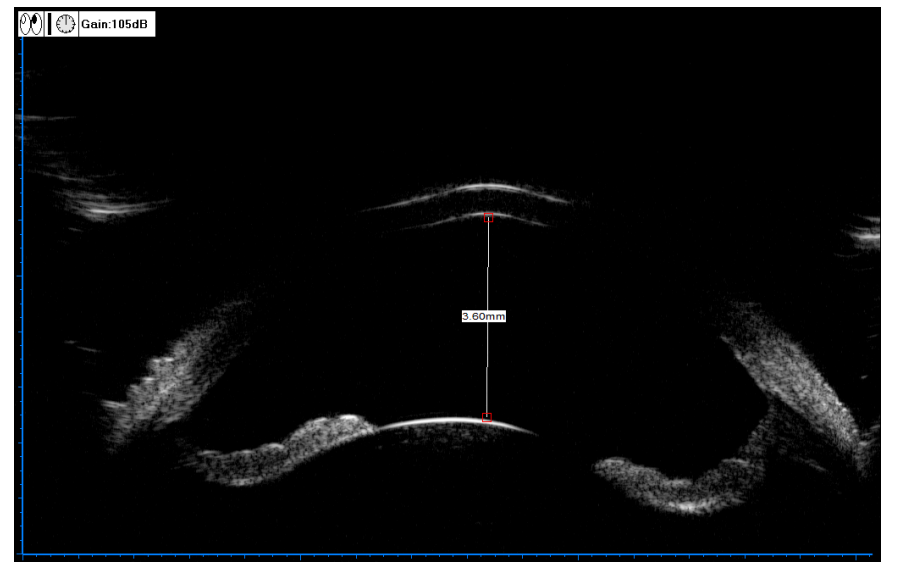

20230221164600_4439.png

图 3 眼部 B 超图像

Figure 3 Ultrasound image of the eye

B 超提示少量后房出血、玻璃体积血。

Ultrasound showed a small amount of posterior chamber hemorrhage and vitreous hemorrhage.